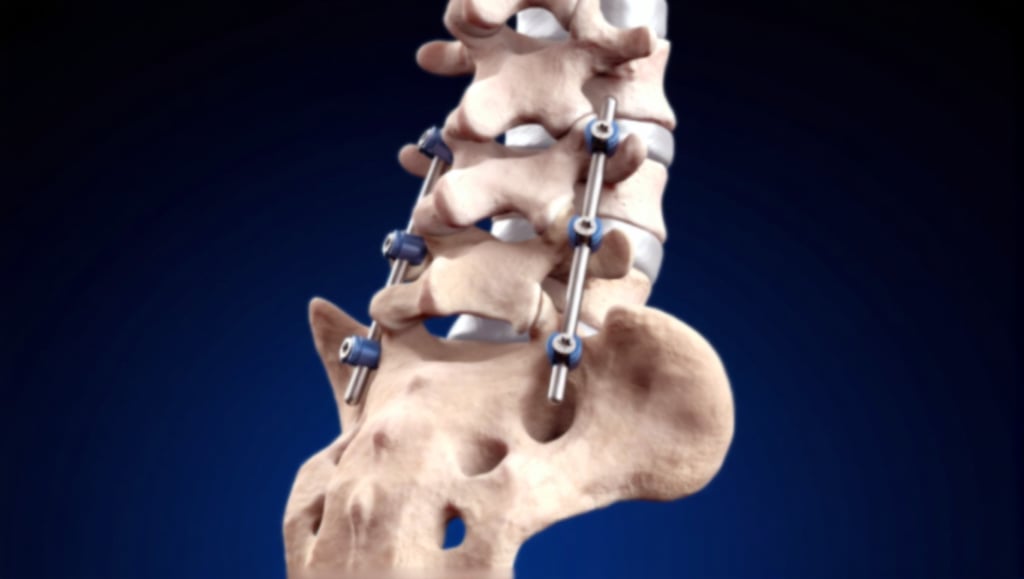

Spinal Fusion Surgery

A surgical procedure that permanently connects two or more vertebrae to eliminate motion between them. Used to treat instability, severe degenerative disc disease, spinal deformities, or spondylolisthesis by creating a solid bridge of bone—stabilizing the spine, relieving pain, and preventing further progression of the condition.